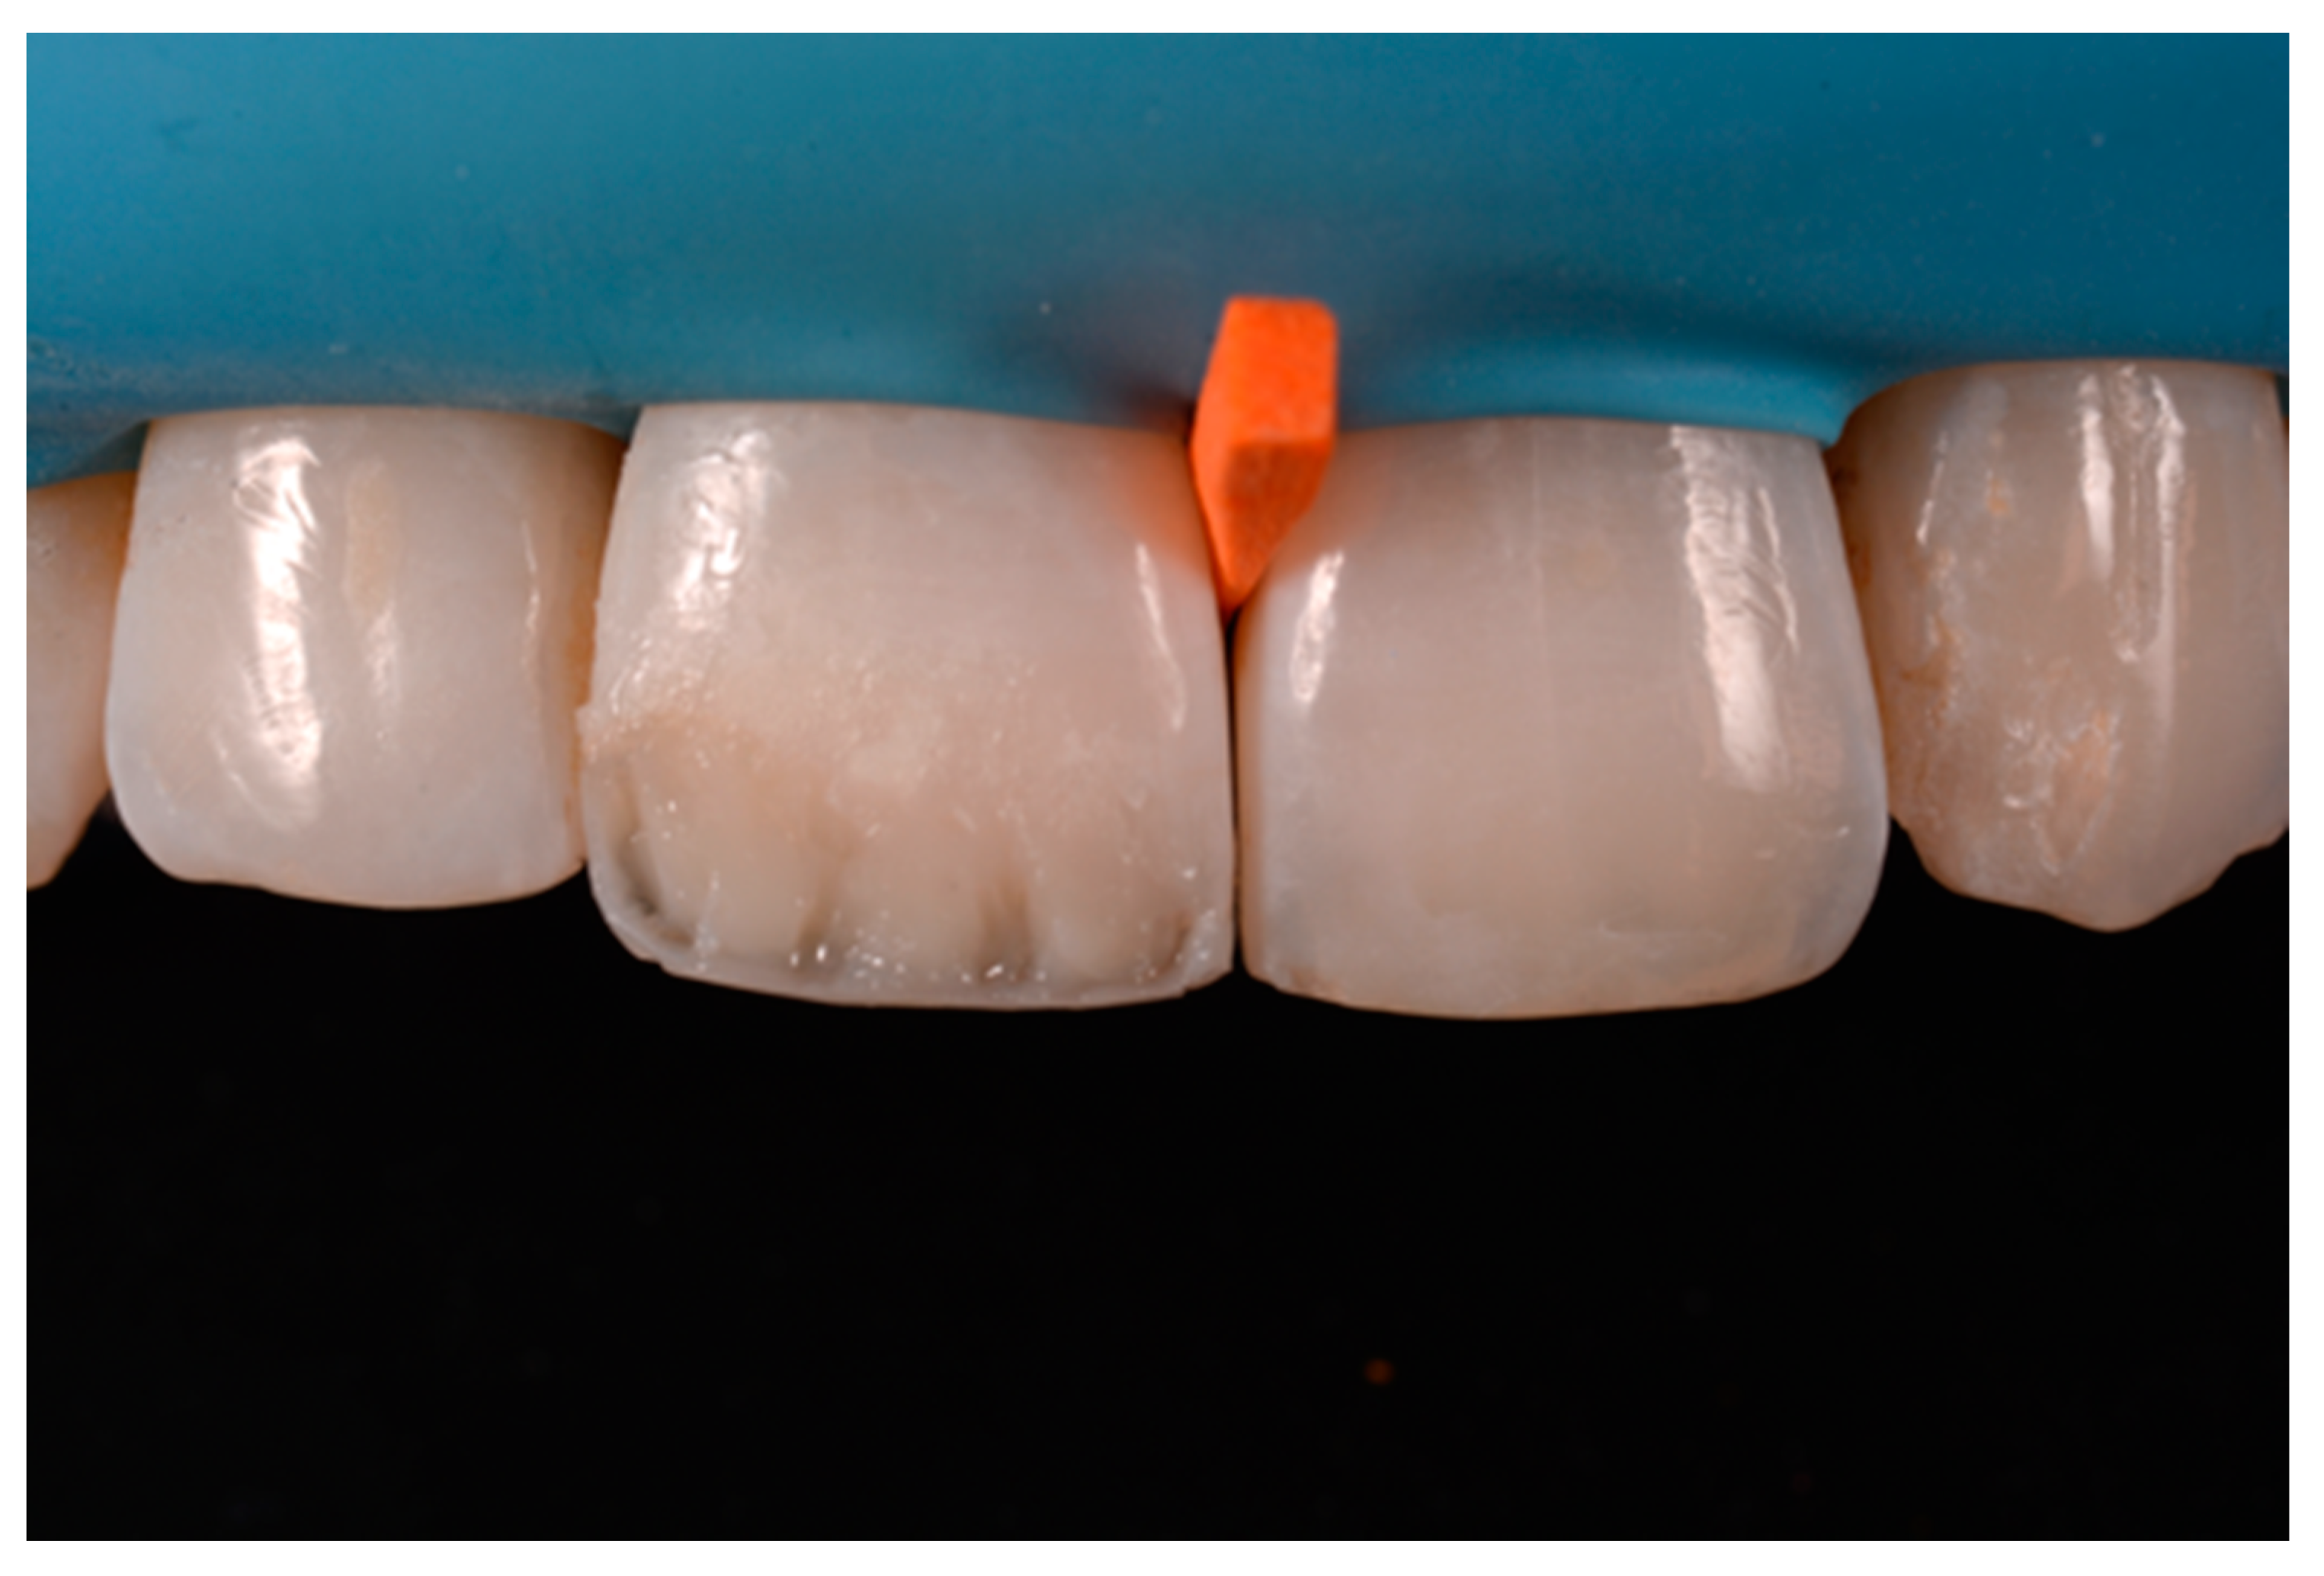

A 53-years old man presented to the dental office asking for the restoration of the mesial incisal angles of both central incisors (Figure 40). After preliminary shade analysis (using the button-try technique [14]) an attentive management of opaque and translucent shades was required to esthetically solve this case. After isolation with rubber dam, preparation, and adhesive procedures (Optibond FL, Kerr, Bioggio, Switzerland) the frame was completed using a translucent shade (Mosaic, ET, Ultradent Products, South Jordan, UT, USA) for palatal wall and an opaque material (Mosaic, A2, Ultradent Products, South Jordan, UT, USA) for incisal margin and interproximal walls. The external and internal excesses of the frame were modified (as described in Section 2.1.2) to obtain a uniform thin opaque outline as planned during the preliminary color/opacity analysis. This modification was performed to avoid the unfavorable uncovering of translucent areas during final finishing procedures that could result in an unaesthetic outcome. Once the definition of the external frame was completed, the mesial mamelon was modeled (Mosaic, A2, Ultradent Products, South Jordan, UT, USA) and the translucent material (Mosaic, ET, Ultradent Products, South Jordan, UT, USA) was applied. Finishing and polishing procedures (Jiffy, Ultradent Products, South Jordan, UT, USA) were completed afterwards.

Figure 40.

Pre-operative, restorative procedures and post-operative of #1.1 and #2.1. Reprinted from Restauri diretti nei settori anteriori, G. Paolone, S. Scolavino, © 2021, with permission from Quintessence Publishing Italy.